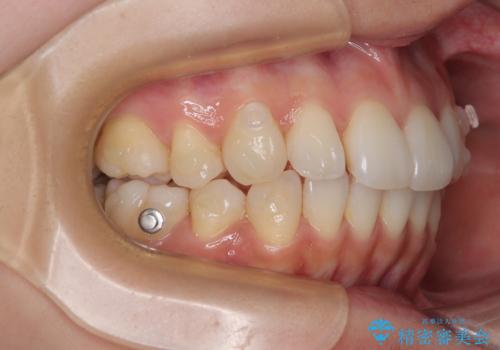

1. 抜歯矯正の軽度後戻りを解消 インビザライン矯正の治療前

2. 抜歯矯正の軽度後戻りを解消 インビザライン矯正の治療中

3. 抜歯矯正の軽度後戻りを解消 インビザライン矯正の治療後